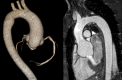

Elective root replacement in Marfan syndrome has improved life expectancy in affected patients. Three forms of surgery are now available: total root replacement (TRR) with a valved conduit, valve sparing root replacement (VSRR) and personalised external aortic root support (PEARS) with a macroporous mesh sleeve. TRR can be performed irrespective of aortic dimensions and a mechanical replacement valve is a secure and near certain means of correcting aortic valve regurgitation but has thromboembolic and bleeding risks. VSRR offers freedom from anticoagulation and attendant risks of bleeding but reoperation for aortic regurgitation runs at 1.3% per annum. A prospective multi-institutional study has found this to be an underestimate of the true rate of valve-related adverse events. PEARS conserves the aortic root anatomy and optimises the chance of maintaining valve function but average follow-up is under 5 years and so the long-term results are yet to be determined. Patients are on average in their 30s and so the cumulative lifetime need for reoperation, and of any valve-related complications, are consequently substantial. With lowering surgical risk of prophylactic root replacement, the threshold for intervention has reduced progressively over 30 years to 4.5 cm and so an increasing number of patients who are not destined to have a dissection are now having root replacement. In evaluation of these three forms of surgery, the number needed to treat to prevent dissection and the balance of net benefit and harm in future patients must be considered.